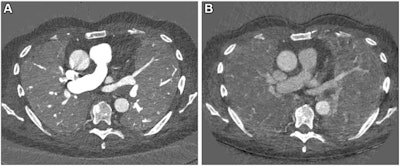

Images in a 67-year-old male patient with slowly progressing idiopathic pulmonary fibrosis. The axial images show differences in the perfusion images generated with (A) photon-counting CT (PCCT) versus (B) standard dual-energy CT. The dose was slightly lower with PCCT (inspiration and expiration, respectively: CT dose index, 3.26 and 3.27 mGy; dose-length product, 126 and 128 mGy∙cm) versus dual-energy CT (inspiration and expiration, respectively: CT dose index, 4.52 and 3.28 mGy; dose-length product, 167.6 and 121.5 mGy∙cm). The technical advancement of PCCT results in improved spatial and contrast resolution. The faster spectral imaging of PCCT also allows for CT pulmonary angiography in addition to a stable, uniform parenchymal contrast. Furthermore, the morphologic images can be reconstructed with high spatial resolution (1024×1024). Images and caption courtesy of the RSNA.The group conducted a study that included 166 patients with interstitial lung disease and post-COVID conditions; each individual underwent a contrast-enhanced inspiratory PCCT followed by expiratory PCCT after a delay of 5 minutes between November 2021 and June 2022.